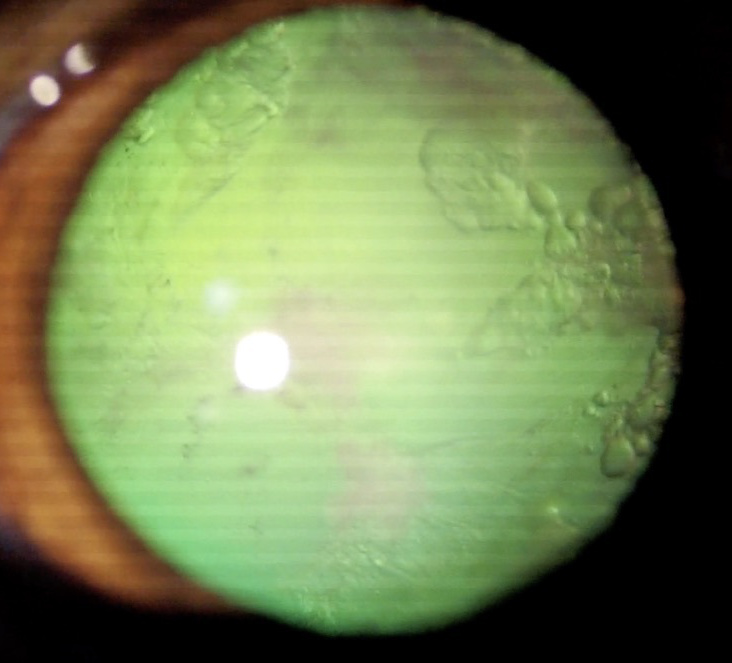

白内障(成熟)

白内障手術前

白内障手術1ヶ月後